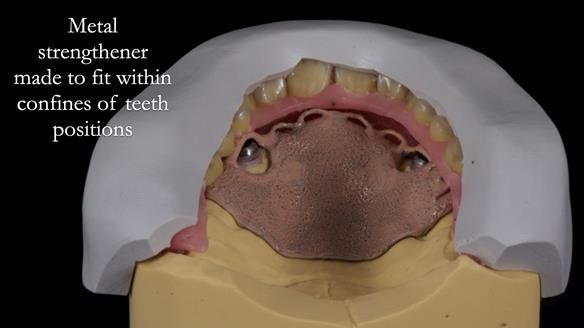

2. The upper denture, horseshoe-shaped and metal-reinforced, rocks on the ridge, causing wear on Locator abutments and a fractured upper right tooth.

The detailed clinical situation and treatment process are outlined below, with clinical work provided by me and technical work by Rowan Garstang. New complete implant supported complete dentures were made. The new upper denture had ‘almost’ full palatal extension for the non-splinted implants following ITI guidelines. A decision was reached to retain the worn Kerator attachments, as their removal could potentially accelerate implant failure. The treatment spanned five visits for denture fitting and one review. Alisdair expressed great satisfaction with the treatment, noting a significant enhancement in his overall quality of life.